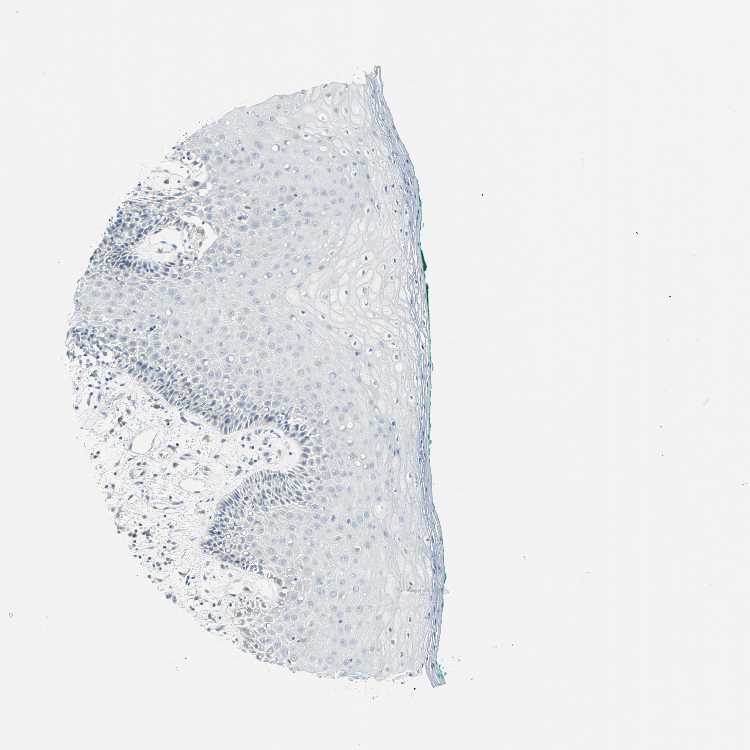

TISSUE PRIMARY DATA ORAL MUCOSA Show tissue menu

ORAL MUCOSA - Antibody stainingi

Antibody staining in the annotated cell types in the current human tissue is reported as not detected, low, medium, or high, based on conventional immunohistochemistry profiling in selected tissues. This score is based on the combination of the staining intensity and fraction of stained cells.

Each image is clickable and will lead to virtual microscopy that enables deeper exploration of all samples and also displays staining intensity scores, fraction scores and subcellular localization as well as patient and tissue information for each sample.

Antibody HPA017919Antibody HPA019649Antibody HPA027734Antibody CAB006246

Squamous epithelial cells Not detectedHighLowNot detected